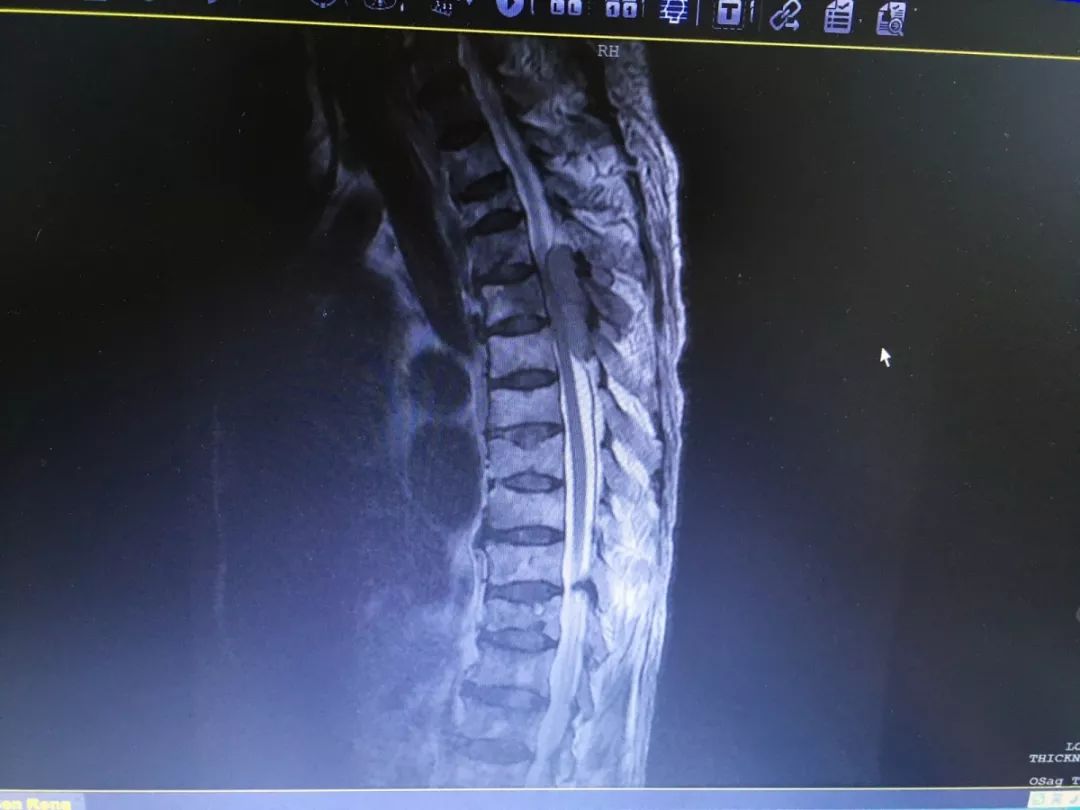

胸椎肿瘤术前

胸椎肿瘤术后